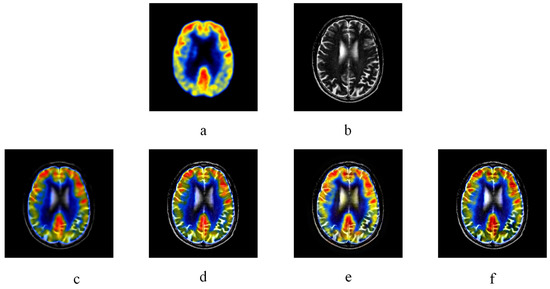

3.2.1. Experiment Results of Medical Images